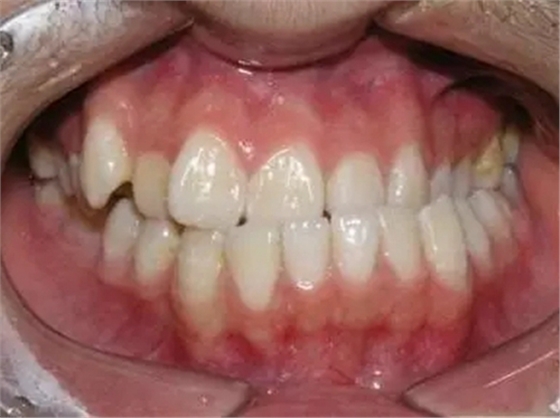

1、錯(cuò)合畸形、咬合關(guān)系紊亂

由于反復(fù)向一側(cè)運(yùn)動(dòng),使下前牙的正中線向一側(cè)錯(cuò)位從而導(dǎo)致后邊的牙齒形成刃對刃、尖對尖的咬合,甚至反咬合(下牙包上牙)。

2、導(dǎo)致大小臉

總是固定用一側(cè),該咀嚼側(cè)經(jīng)常得到鍛煉,促進(jìn)了頜骨及肌肉的發(fā)育,因而該側(cè)面部組織豐滿。經(jīng)常不用或少用的那一側(cè)因缺乏鍛煉使面部組織發(fā)育較差、萎縮變小,從而造成發(fā)育不對稱,一邊臉大,一邊臉小。